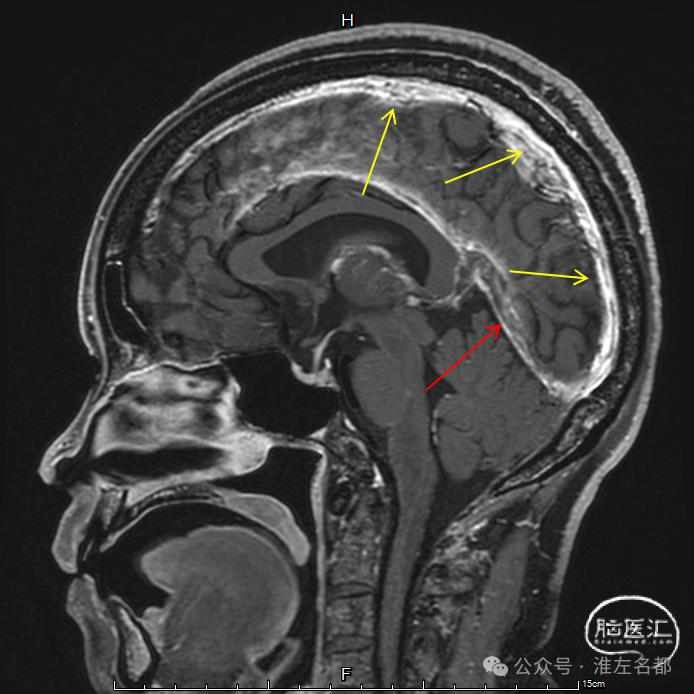

T2

T1

FLAIR

DWI

双侧丘脑和右侧内囊-间脑淤血性梗死、水肿和伴渗血。

增强MRV:左侧横窦-乙状窦显影纤细;上矢状窦和右侧横窦-乙状窦充盈缺损;脑深部静脉和直窦未见显影。

SWI:双侧丘脑渗血改变,右侧基底静脉和大脑中静脉血栓。